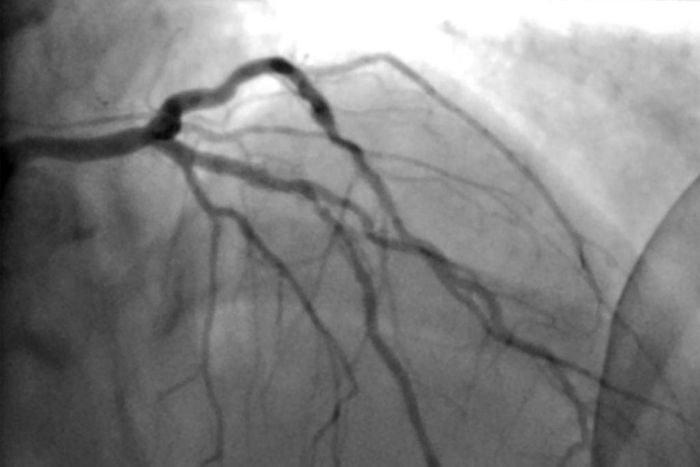

When an exercise stress test indicates a narrowing, most doctors send patients to a cardiac catheterization lab to look for blockages, Maron said. If there is a blockage, the usual practice is to open it with a stent.

If stenting is not feasible — because of the configuration of the patient’s arteries, for example — bypass surgery is usually the next step.